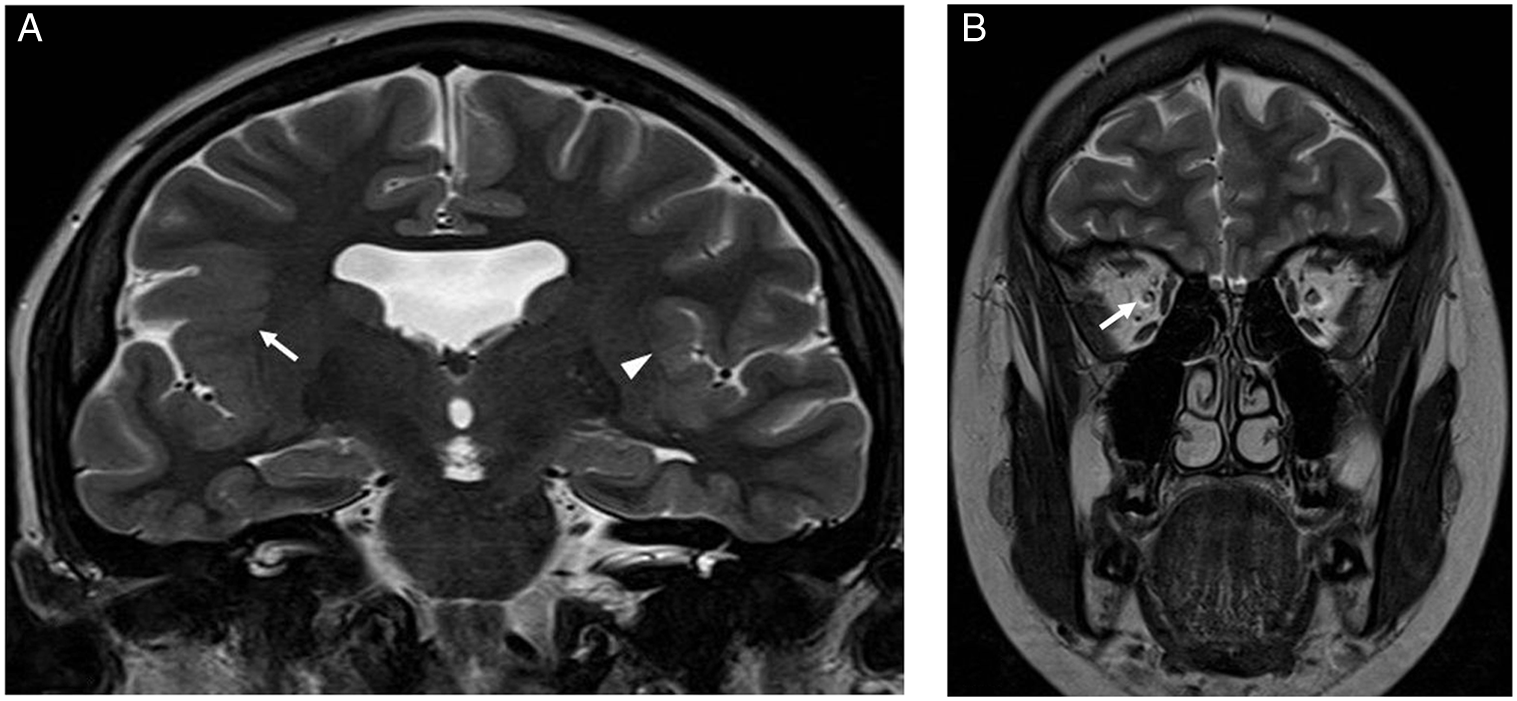

Septo-optic-pituitary dysplasia (SOD) is a neurodevelopmental abnormality that consists of optic nerve(s) hypoplasia (ONH) in association with hypopituitarism and/or midline brain abnormalities (absent septum pellucidum and/or abnormal corpus callosum) (Figures 1 and 2). In addition, neuronal migration disorders (NMD) (Figure 3) have been reported in some patients with SOD. ONH may also occur in isolation. Reference Garcia-Filion and Borchert1,Reference Webb and Dattani2

Figure 3: Brain MRI images of a 17-year-old female with impaired vision of the right eye and focal epilepsy arising from the right cerebral hemisphere. (A) Coronal T2-weighted image showing absent septum pellucidum and polymicrogyria involving the left perisylvian region (arrow head) and right fronto-parietal-temporal lobes including the sylvian fissure (arrow). (B) Coronal T2-weighted image of the orbits showing a small right optic nerve (arrow).

There were 128 patients (M = 70) with ONH/SOD who had neuroimaging studies. Their median age (interquartile range) at study end was 12.2 (7.4–17.6) years. Their neuroimaging characteristics and findings are displayed in Table 1. Figures 1 –3 show some of the abnormal neuroimaging features.